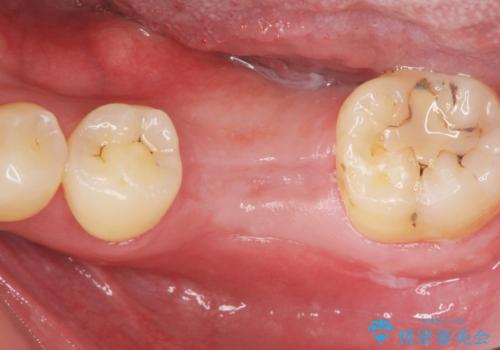

- 「長年虫歯放置した結果、抜歯となってしまった左下奥歯に歯を入れたい」、と希望され来院されました。

前後の歯は虫歯も治療歴もないため、前後の歯を削らなくてはいけないブリッジではなくインプラント治療による咬合機能回復を計画します。